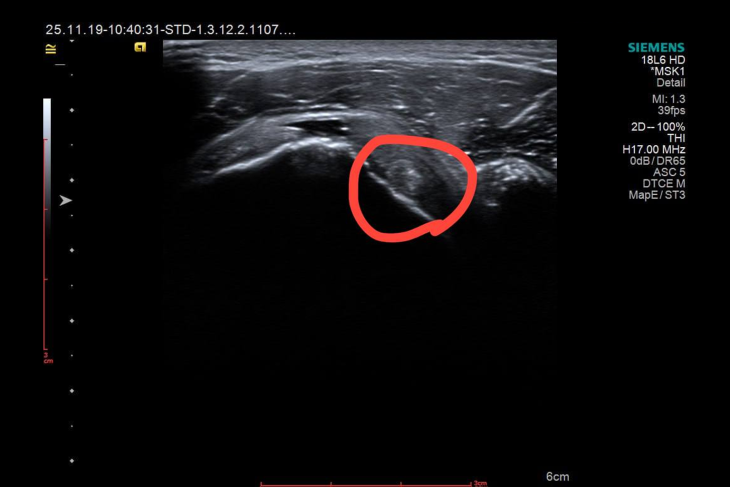

Результати аналізів виявилися в межах норми — не виявлено запальних змін. Клінічне обстеження не виявило розпухших суглобів, за шкалою DAS 28 2.67 — низька активність хвороби. А ось УЗД плечового суглоба виявило цікаві знахідки, які повністю змінили подальшу тактику.

У ході дослідження були виявлені:

В представленому клінічному випадку УЗД дозволило побачити розрив, кальцинат, виключити капсуліт та синовіт, оцінити біомеханіку суглоба в реальному часі і довести, що рутинний біль у плечі ніколи не варто розглядати як банальність.